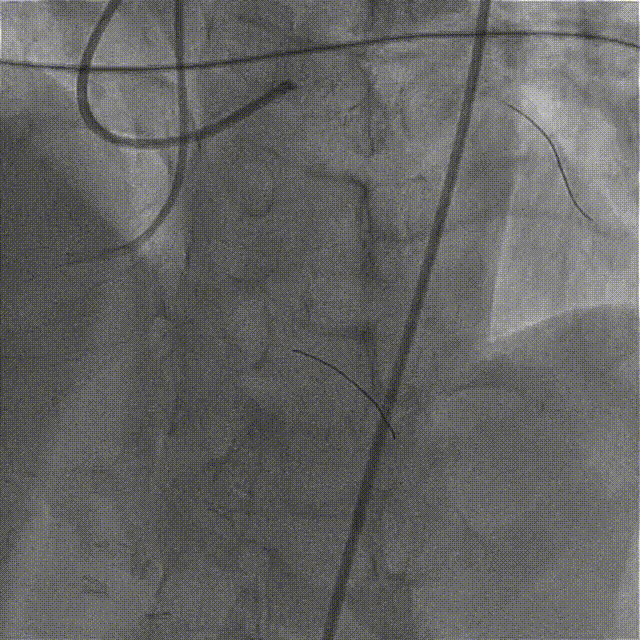

在HighTrack微导管的支撑下及逆向导丝的指引下,正向用Gaia First、Gaia Third、PILOT 200导丝反复尝试,均未能通过闭塞段进入血管真腔。

逆向重新送入一根SION Blue导丝反复尝试,最终进入正向指引导管内,推送逆向微导管至正向指引导管内,逆向送入RG3导丝至正向入口,正向沿RG3导丝推送微导管至LAD远段,撤出逆向导丝及微导管,交换一根SION Blue导丝至LAD远段。